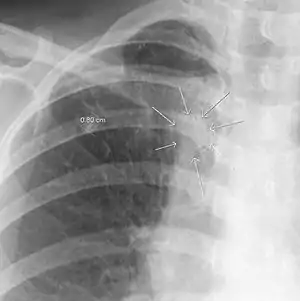

In radiology, the air crescent sign is a finding on chest radiograph and computed tomography that is crescenteric and radiolucent, due to a lung cavity that is filled with air and has a round radiopaque mass.[1] Classically, it is due to an aspergilloma, a form of aspergillosis, that occurs when the fungus Aspergillus grows in a cavity in the lung.[2] It is also referred as Monad sign.[3]

| The arrows denote an ill-defined nodular opacity in medial aspect of right upper lobe with ill-defined rim of lucency surrounding it | |

| Differential diagnosis | Aspergilloma |